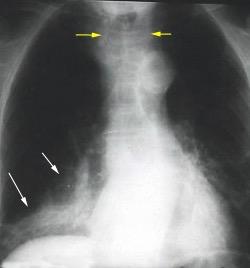

Triada de Garland

Ganglios paratraqueales derechos e hiliares bilaterales

95% de pacientes tienen ganglios hiliares bilaterales aislados o con afectación mediastínica (espec. paratraqueal derecho).

Criado E et al. Pulmonary sarcoidosis: typical and atypical manifestations at high-resolution CT with pathologic correlation. Radiographics. 2010